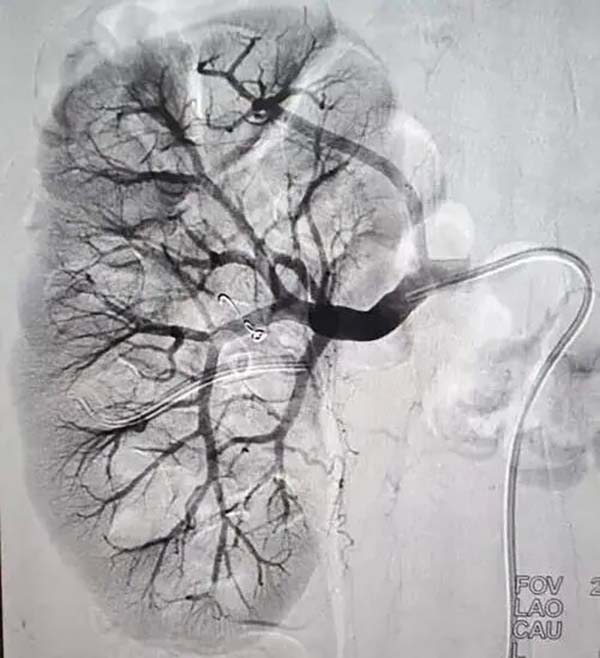

【杨柳科普】“我的10个单位的肾小球滤过率去哪儿了?” | 揭秘介入术后肾功能下降的真相

前几天,一位刚做完下肢血管介入手术的患者,拿着术后复查的化验单,一脸困惑地问我:“杨医生,我术前肾小球滤过率是85,现在是75,这10个单位的‘肾功能’,它们到底去哪了?是被造影剂吃掉了?还是被手术‘偷’走了?”

二、造影剂不是“毒药”,但它是“压力测试”

但它就像一个“压力测试”。它本身不直接“杀死”肾细胞,但它会增加肾脏的“工作负荷”。它需要通过肾脏排泄,这个过程会消耗大量的能量和氧气,让肾脏“加班加点”工作。对于一个“身强体壮”的肾脏,这点“加班”不算什么。但对于一个“年老体弱”或“本就带病”的肾脏(比如有糖尿病、高血压、慢性肾病),这“加班”就可能让它“累趴下”,导致肾小球滤过率暂时性下降。